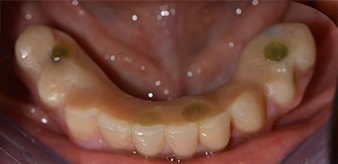

The 64-year-old patient presented with residual dentition of teeth 38, 33 and 43 and a clasp denture in the mandible (Fig. 1 and 2).

Fig. 2